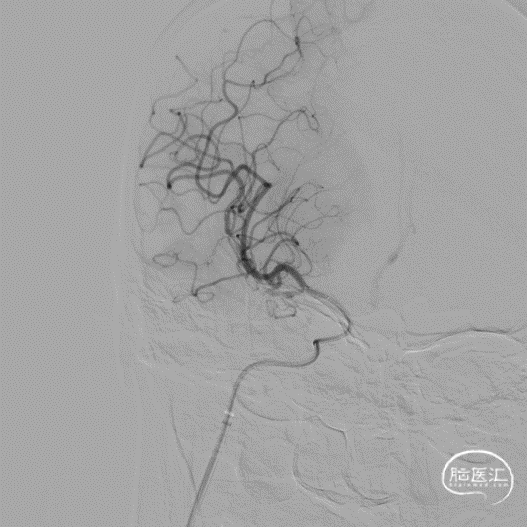

Tethys®中间导引导管到达大脑中动脉血栓部位,边抽边撤Tethys®中间导引导管,未见血栓;Tethys®中间导引导管再次到位大脑中动脉,微导丝微导管通过闭塞段,微导管造影证实在真腔。

释放3*25mm Syphonet®取栓支架,停留5分钟后撤出Syphonet®取栓支架并保持负压抽吸,第一次复查造影血流未通。

再次重复上述操作,释放Syphonet®取栓支架并停留5分钟后撤出取栓支架并保持负压抽吸,再次复查造影右侧大脑中动脉下干血流恢复,mTICI血流3级。